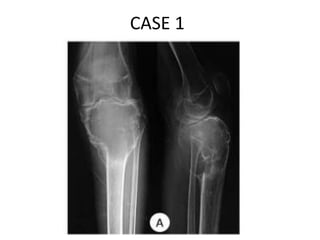

CASE 1

CASE 2